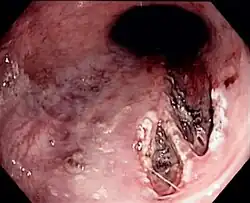

| Mallory–Weiss tear affecting the esophageal side of the gastroesophageal junction | |

Definitive diagnosis of Mallory-Weiss tears is by upper GI endoscopy of the esophagus and stomach.[2][30] Typically, the tear is located near the top of the stomach's lesser curvature and below the gastroesophageal junction. In the majority of patients, tears usually range from approximately 2 to 4 cm in length. The findings may include indications of non-bleeding, active bleeding, or the presence of clot over the tear.[2] Furthermore, an upper GI endoscopy can reveal underlying conditions that lead to the signs of bleeding secondary to the tears, including varices and ulcers along the upper GI tract.[2] To determine if the patient has active bleedings or signs of chronic alcoholism that can precede Mallory–Weiss syndrome, the patient's lab values would be obtained to get a complete blood count (CBC) including hematocrit & hemoglobin levels alongside platelet count.[2] Additionally, diagnosis of Mallory-Weiss Syndrome includes elimination of other causes of an upper gastrointestinal bleed and/or bleeding in general. For example, a patient should undergo more labs to determine kidney function via measuring blood urea nitrogen and creatinine as a patient with chronic kidney disease can be mistaken to have active bleeding due to anemia induced by chronic kidney disease or if both the esophageal lacerations and chronic kidney disease are contributing to the low hematocrit & hemoglobin levels.[2][31]